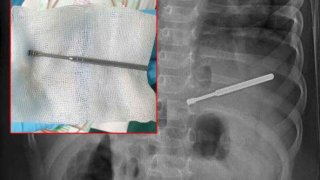

"หนูน้อยวัย 2 ขวบที่มีอาการปอดบวม" ผลเอกซเรย์เจอไม้แคะหู